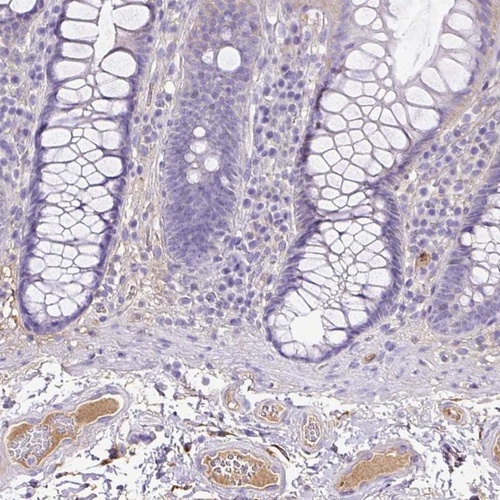

Immunohistochemical staining of human colon shows distinct plasma positivity.